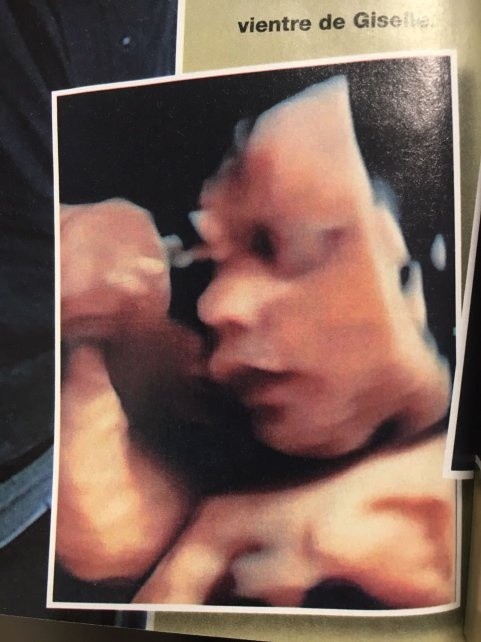

Además, mostró por primera vez el rostro de su bebé en la última ecografía 4D.